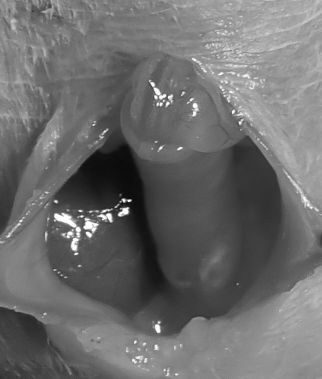

来院時の様子より腸重積と診断、すぐに開腹手術を実施しました。

お腹を開くと、腸が腸の中に入り込んでしまっているのが確認できました。